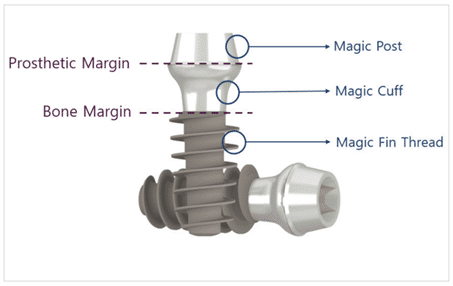

(Figure 1) Schéma de l’implant MagiCore.

MagiCore est un implant tout-en-un composé de trois parties : le Magic Fin Thread, le Magic Cuff (col) et le Magic Post (figure 1). Dans cet article, nous expliquerons les principes de développement de MagiCore dans l’ordre suivant : 1. Le Magic Cuff, 2. Le Magic Fin Thread et 3. Le Magic Post.